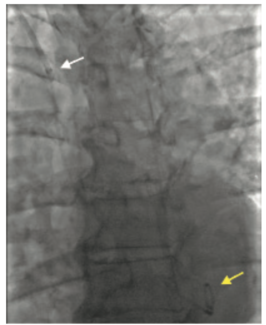

An 80-year-old female with a history of heart failure with reduced ejection fraction, hypertension, and chronic kidney disease presented with worsening dyspnea and fatigue for 6 months despite being on optimal guideline-directed medical...